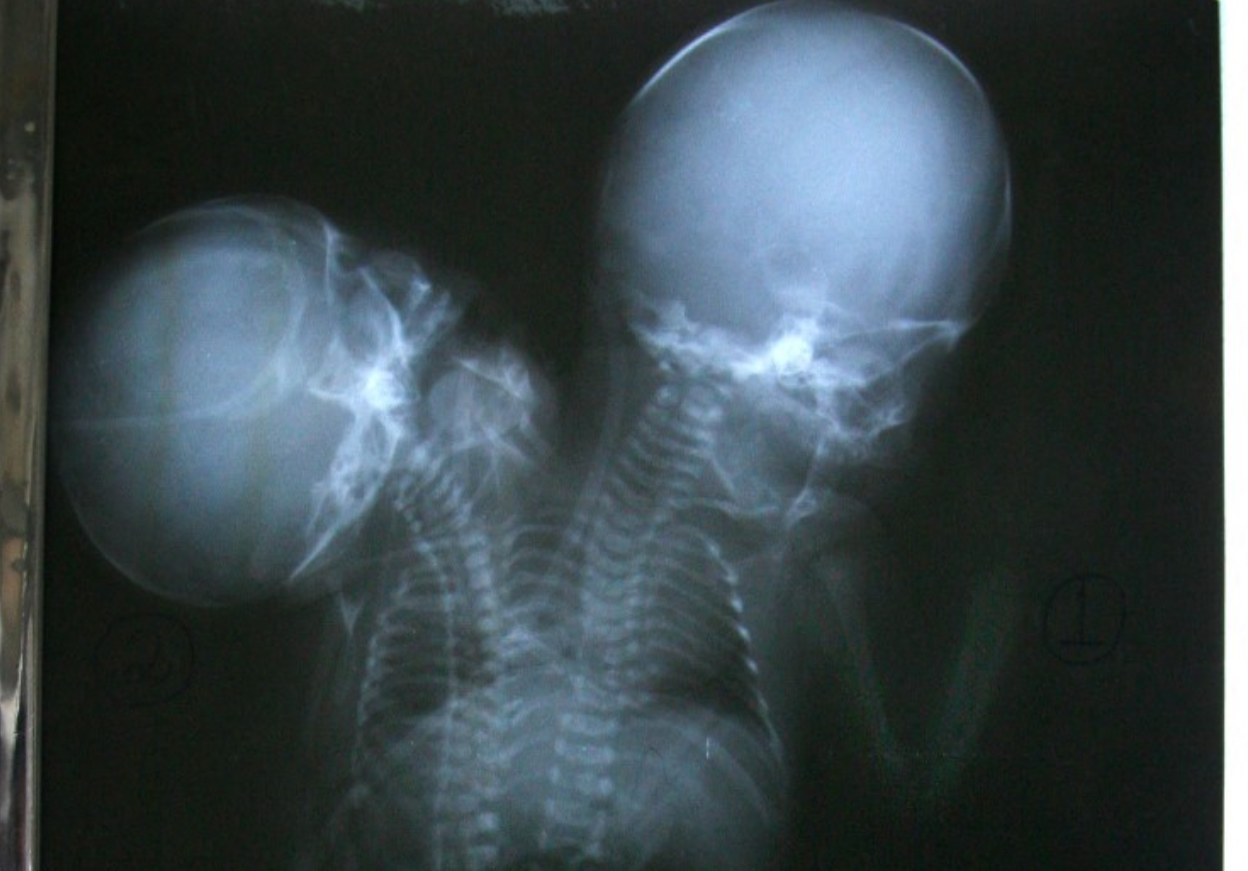

"Conjoined twin pregnancies can be identified as early as the 10th to 12th week of gestation, but the majority of the cases in Malaysia are detected at around 20 weeks of pregnancy.

"The survival rate for conjoined twin pregnancies is only between five and 25 per cent, and early detection is crucial in determining whether to continue or terminate the pregnancy,” she said after attending the launch of the International Conference on Conjoined Twins 2024 here today.

Dr Roziah added that early detection also enables the medical team to better plan the surgery for delivery based on the condition of the conjoined twin foetuses.